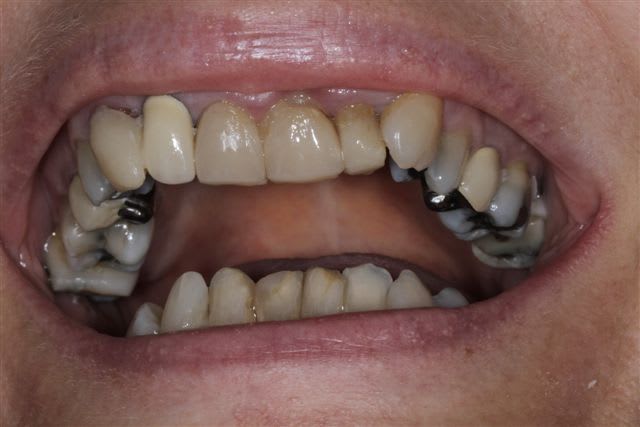

N'hésitiez pas çà me donner votre avis, patiente 47 ans ne supporte plus ses antérieurs, maquillées à la résine il y a quelques années.

Pas de demande concernant l'occlusion, ni les postérieurs, à fait des économies et veux s'offrir "un sourire", sur fond propre budget envisageable au départ 4000€

C'est un cas de réhab global, ortho et 28 couronnes.

Les secteurs post sont en mauvais état, l'occlusion est moche, et si tu ne fais que le sourire, tu auras de drôle de résultat et des casses de céram ou bien des antagonistes.

Vu les axes actuels des antérieures, soit tu gardes la même forme et les mêmes axes et tu auras de dents assorties mais pas vriament plus esthétiques. Sinon c'est ortho et la totale. Si tu changes la forme sans amélioration de l'esthétique ce sera l'echec mécanique assuré.

Je suis assez d'accord avec Ceramik, ce qui me saute aux yeux,outre l'esthétique bien sur, ce sont les courbes occlusales de la patiente, notamment secteur 2 et 3 en postérieurs(26 ne semble pas en occlusion, et 27 sur une pointe).

Le secteur antérieur doit donc supporter pas mal de contraintes... d'autant plus que le guide incisif semble assez fermé.

Perso, je ne toucherai à rien en antérieur,( d'autant plus avec du tout céram) tant que les courbes postérieures ne sont pas rétablies.

Il n'y a pas un probleme sur l'occlusion cote gauche type coulure de platre ?